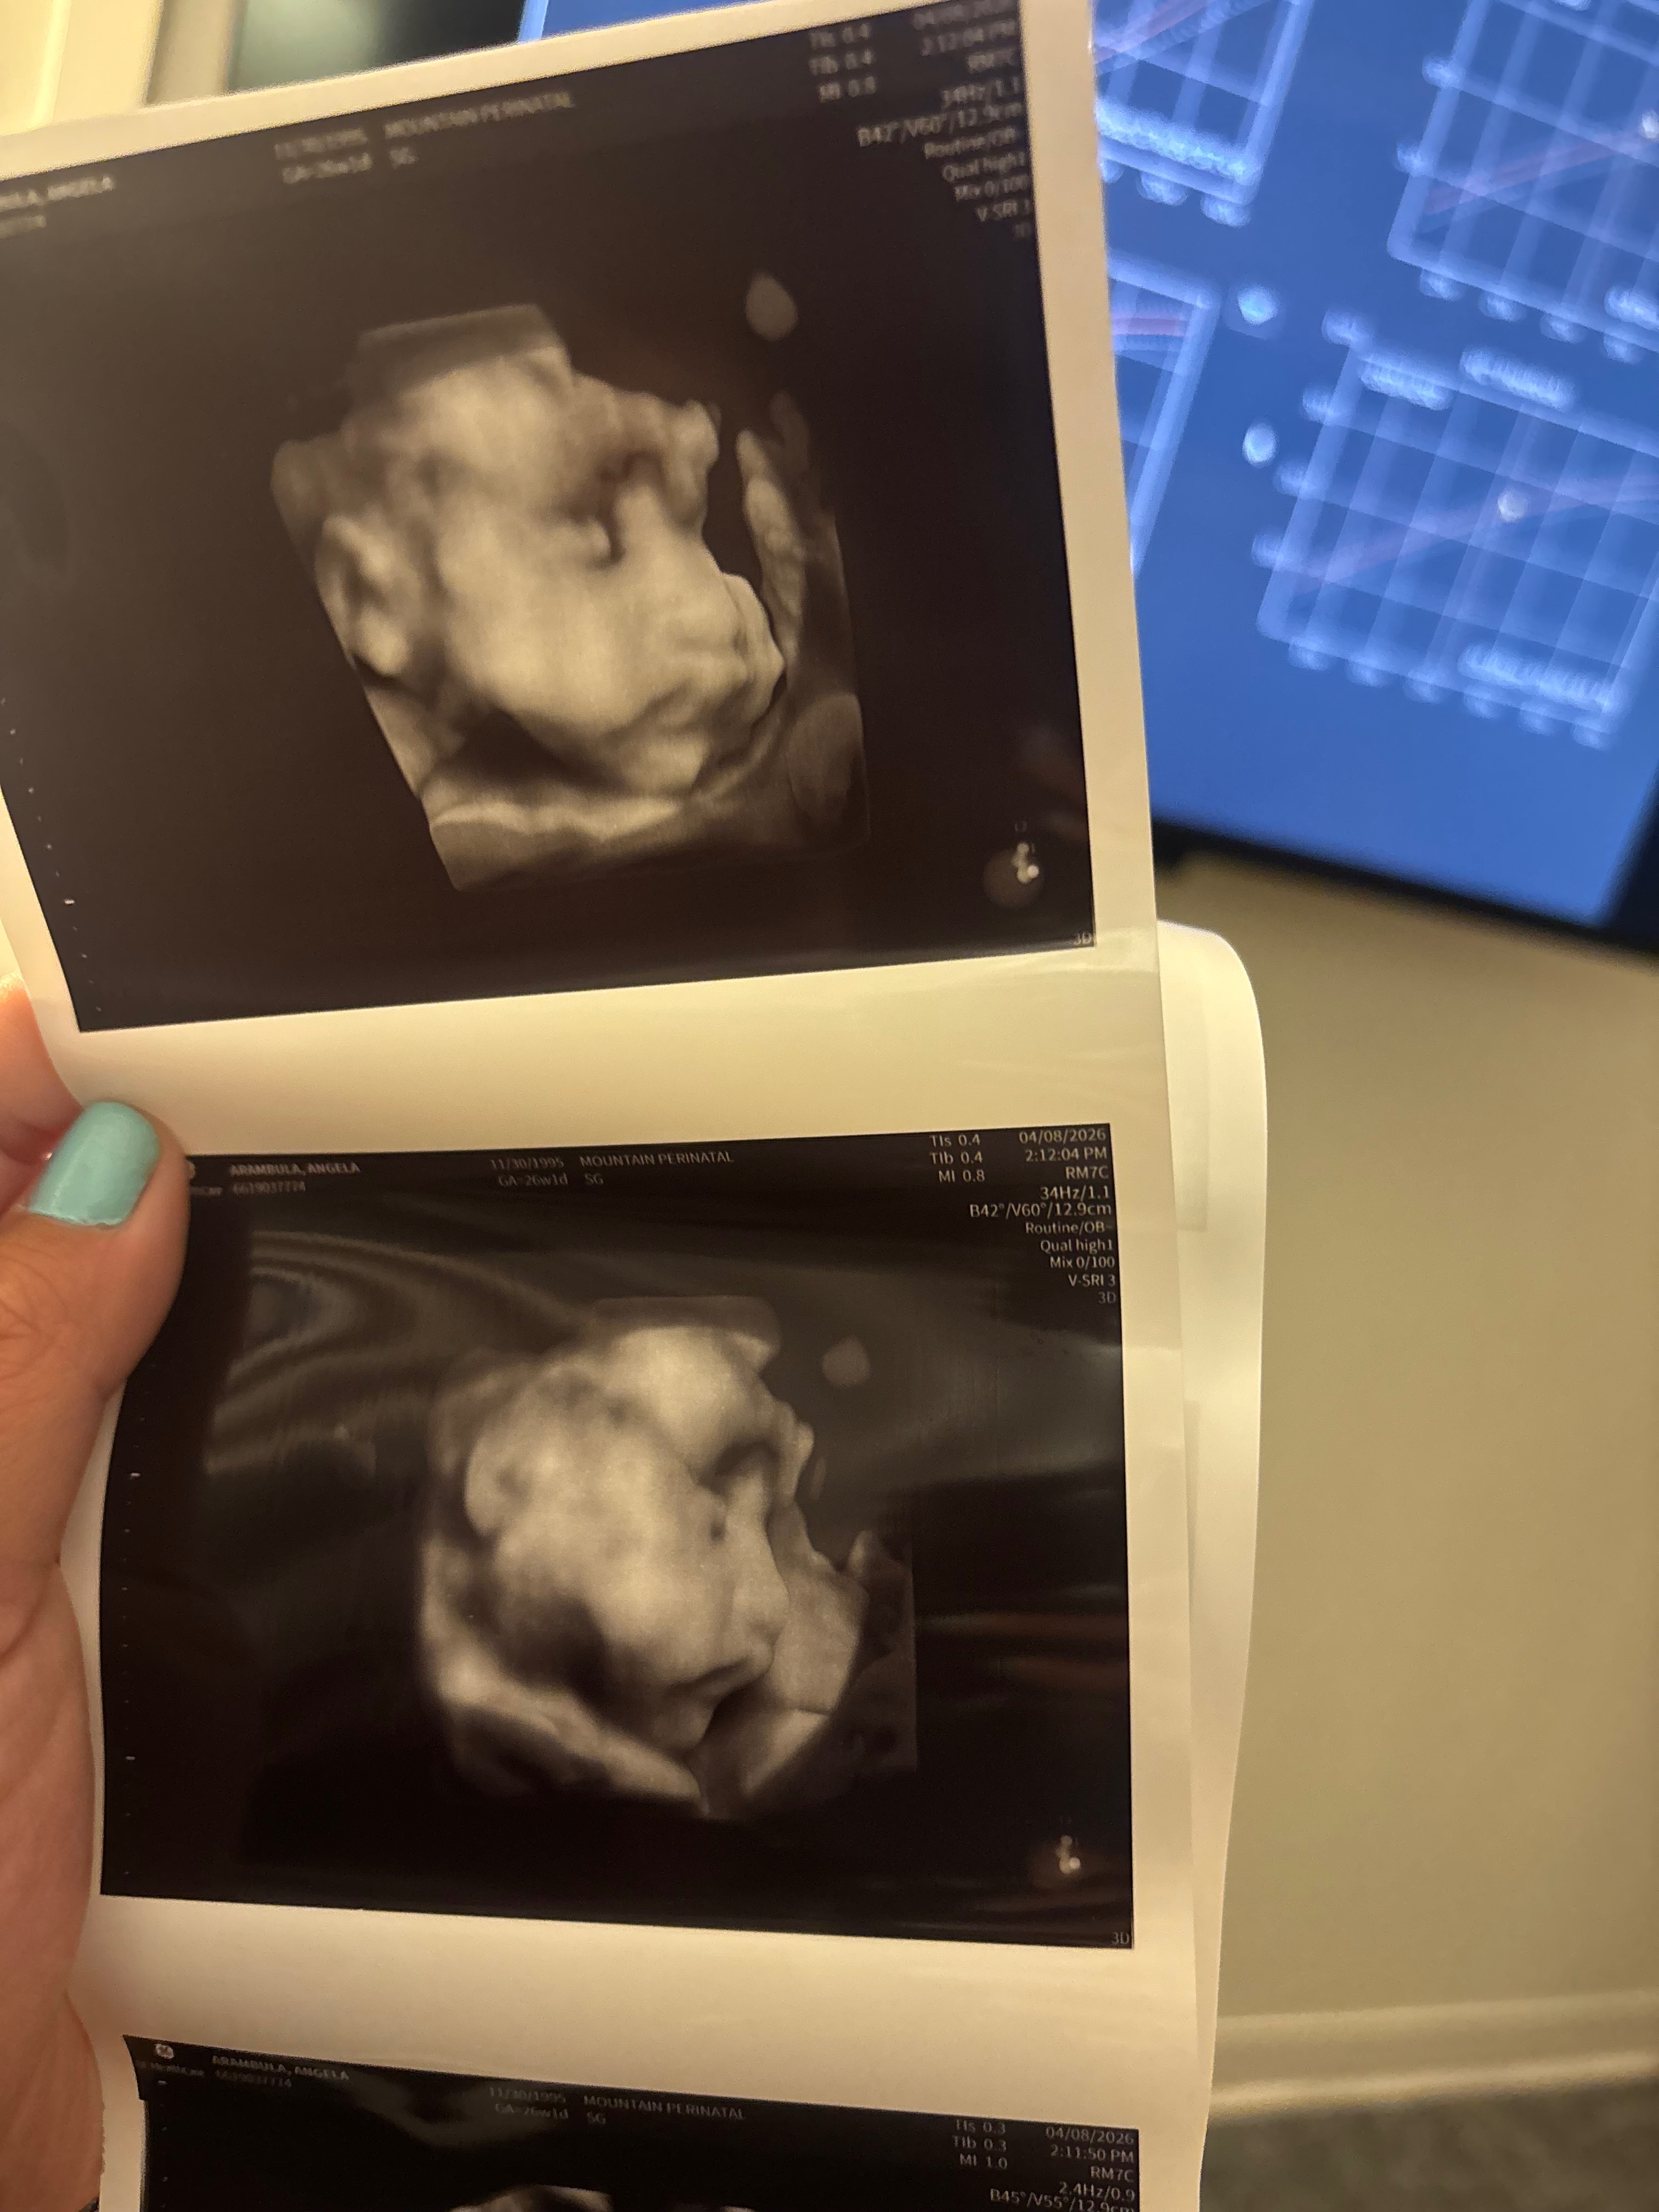

Hello friends and family. Our son has a rare lung lesion called CPAM, which could potentially affect his airway. At 23 weeks gestation, I had to switch OB’s and care team from Bakersfield to Los Angeles for better treatment options. Consequently, I will need to stay in Los Angeles for some time before and after birth, especially if he requires surgery. In light of these circumstances, we kindly request any assistance you can provide to cover the costs associated with our stay, including food, gas, and other expenses. Your support means the world to us as we care for our precious baby boy. We truly appreciate your generosity and compassion. Thank you from the bottom of our hearts. God bless